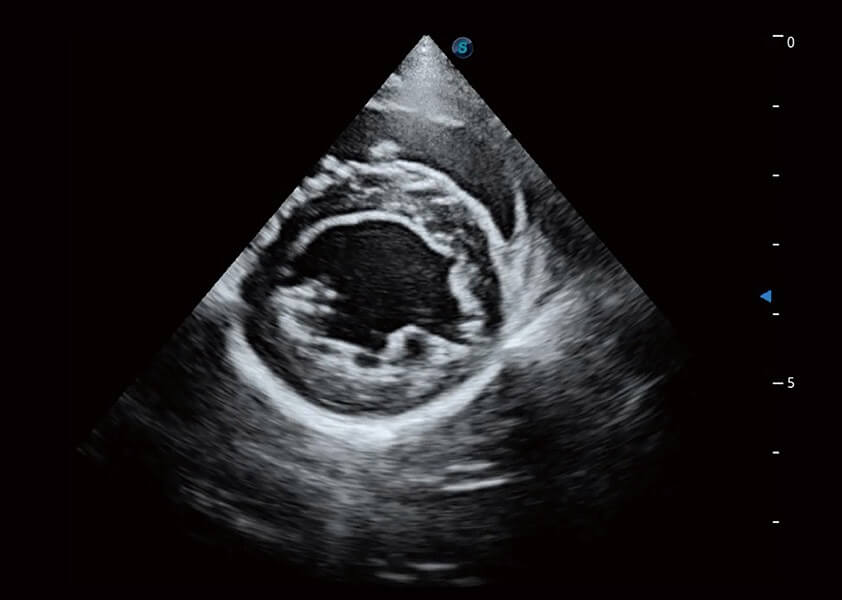

动物是人类最亲密的朋友和最值得信赖的伙伴。亚星官网也一直致力于探索动物专用的超声影像解决方案。 全新推出的ProPet系列,是亚星官网在动物超声影像智能化、专业化、精准化的一次跨越式革新。动物不能用言语来表述自己的不适,通过超声影像,ProPet系列搭建了动物医生与不同物种沟通的“桥梁”,为动物医生注入了“治愈之力”。